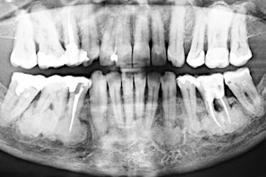

A raiz sumiu: dentes são reabsorvidos

15.03.2025 07h18

COLUNISTA